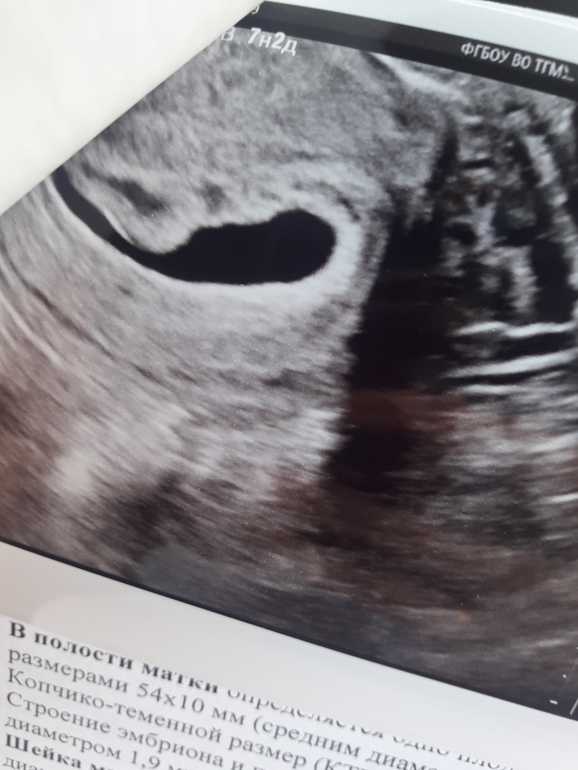

Замершая беременностьНо плодное яйцо это пипец какой формы. По нему говорит врач и срок не определить... На дне жм и что то эхогенное.

а это в "хвосте" у запятой. Вроде как жм